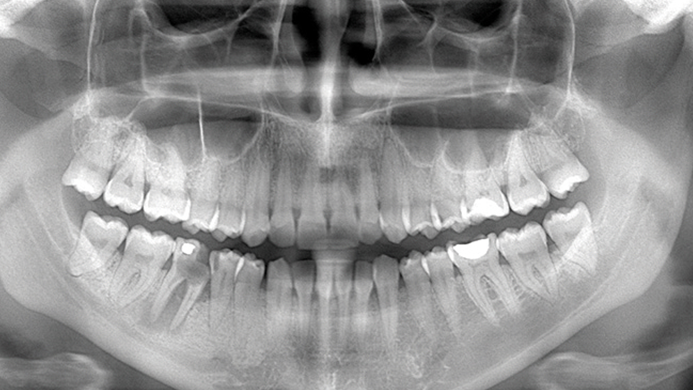

Clinical case: Delayed implant placement: sinus floor elevation by means of lateral

approach & implant placement with GBR

- Courtesy of Dr. Irfan Abas, Netherlands -

Clinical case: # 46 implant placement & GBR using i-Gen membrane for significant vertical resorption & mixed bone defect

- Courtesy of Dr. Iulian Filipov, Romania -